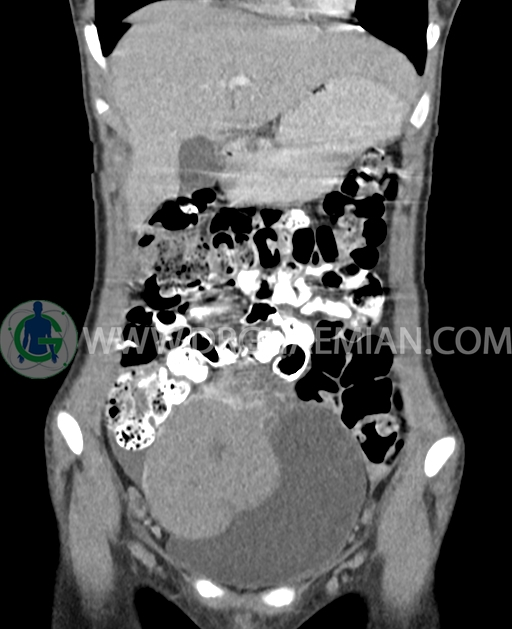

سی تی اسکن شکم و لگن از تشعشعات برای ایجاد تصاویر عرضی مقطعی از نایحه شکم و بین استخوان های لگن استفاده می کند. در این کیس تومور سلول زایا به ابعاد mm 125 x 112 x 80 دیده می شود.

در سی تی اسکن اسپیرال شکم و لگن با کنتراست خوراکی و وریدی (مولتی دیدکتور 16 با مقاطع ظریف و بازسازی های ساژیتال و کرونال) :

توده هیپردنس لوبوله بزرگ به ابعاد 125x112x80mm حاوی نواحی سیستیک داخلی و enhancement قابل توجه پریفرال همراه با آسیت متوسط در فضای شکم و لگن با احتمال بیشتر با منشا از تخمدان راست، درون لگن دیده می شود که در درجه اول مطرح کننده germ cell tumor می باشد .